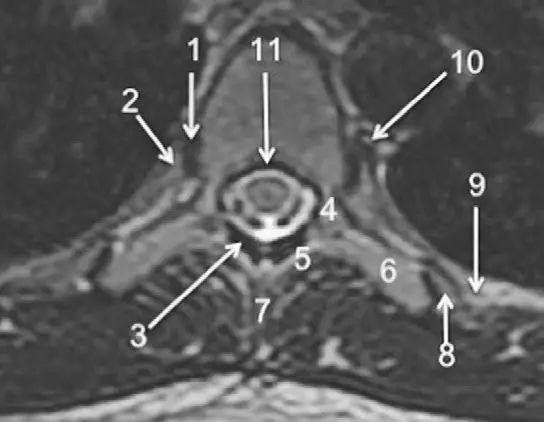

图 2 胸椎 T2WI 轴位图:1,肋椎关节;2,类骨头;3,黄韧带;4,椎弓根;5,椎弓板;6,横突;7,棘突;8,肋横突关节;9,肋结节;10,半奇静脉;11,后纵韧带